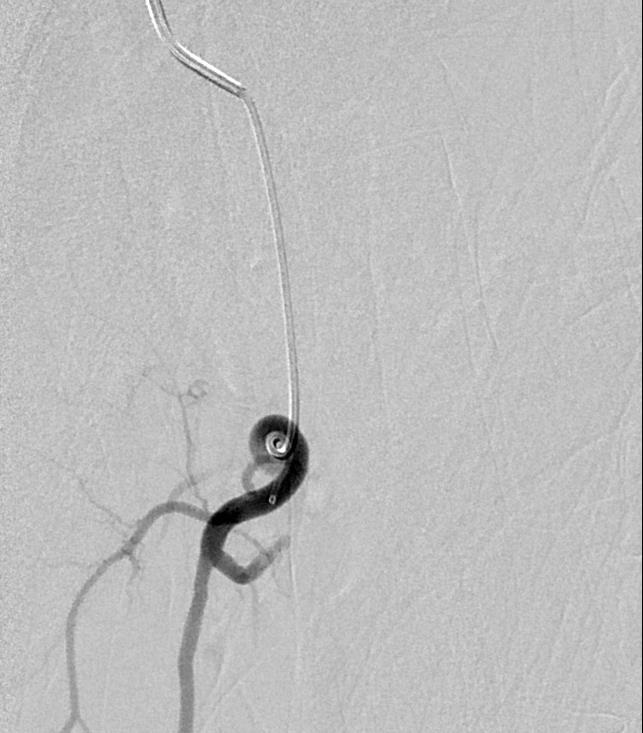

病例1 :"Loop - the . Loop”

![]() |